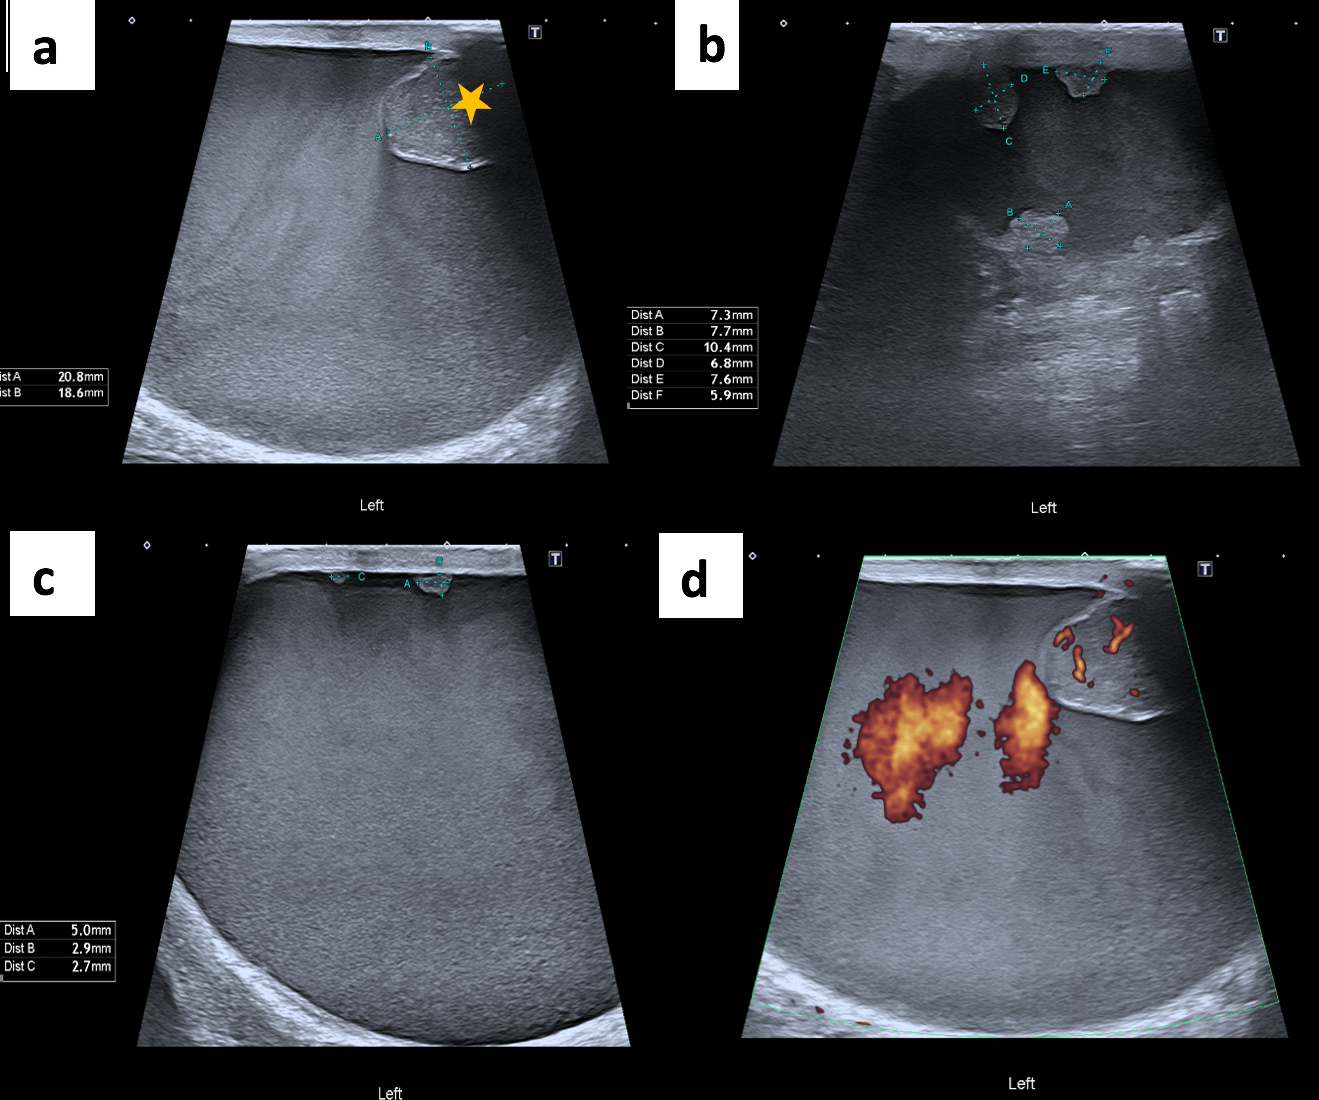

The ultrasound scan revealed turbid fluid with internal echoes and multiple hypoechoic, nodular, excrescences/adherent lesions on the tunica vaginalis. MRI scan was unremarkable.

Ultrasound is the primary imaging modality used to assess scrotal swelling or potential tumours. This is due to its easy availability, use of non-ionising radiation, cost-effectiveness and real-time features. However, ultrasound is highly operator-dependent and, therefore, requires adequate training. Other modalities, such as magnetic resonance imaging (MRI) or computed tomography (CT), can be considered when ultrasound findings are equivocal. Histology analysis of surgically removed (or biopsied) scrotal tumours is the gold standard for diagnosis. Although rare, tumours of the tunica vaginalis include fibrous pseudotumours and malignant mesotheliomas. They both primarily affect middle-aged men and are characterised by painless nodules and scrotal enlargement. The common sonographic appearance suggestive of MMTV includes the presence of singular or multiple painless nodules/excrescences in the tunica vaginalis with hydrocele. The diagnosis in this case was confirmed through orchiectomy followed by histopathology and immunochemistry.